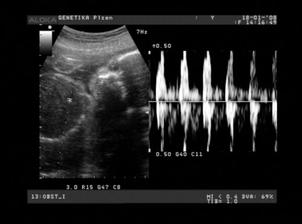

Náš svatební den byl 7.7.2007 a mimísek na sebe nenechal dlouho čekat 🙂 Už 21.8.2007 jsme na testu objevili // a těhu průkazku jsme dostali 12.10.2007. Naše bublinka by se měla narodit na konci dubna, tak uvidíme, kdy se jí bude chtít na svět.